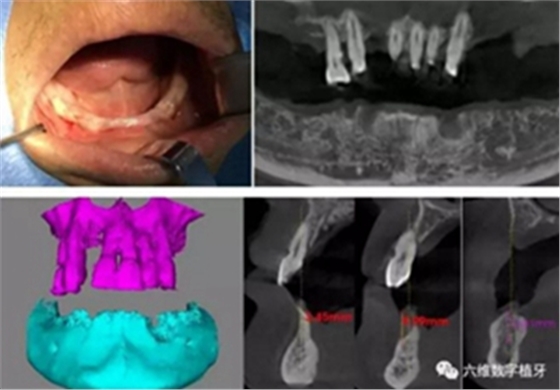

患者男,喜歡抽煙喝茶,有重度牙周病,下頜的牙齒已經(jīng)完全拔除,上頜牙齒在CT中可見,牙槽骨吸收很嚴(yán)重,牙根部分暴露,粘膜萎縮。要求:進(jìn)行下半口固定義齒即刻修復(fù)。

從CT可以看出患者前牙區(qū)牙槽骨非常薄,有的地方3.5mm不到,左側(cè)4號牙位有嚴(yán)重的骨吸收,需要進(jìn)行植骨,后牙區(qū)離神經(jīng)管較近,設(shè)計種植短粗型種植體。